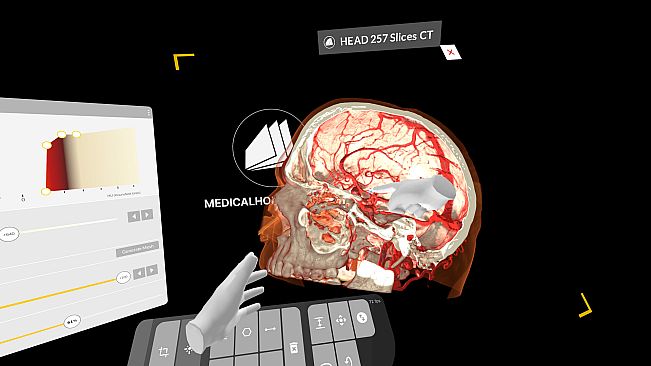

Experience medical education in virtual reality. Explore detailed 3D human dissections and 3D anatomy models. Automatically segment CT scans with AI, and exercise surgeries in an immersive environment.

With advanced tools for surgical simulation, AI-powered segmentation, and anatomy study, you can visualize, manipulate, and collaborate on medical content and images.*

Visualize surgical procedures using patient data. Import medical images and bridge the gap between theory and practice.

AI-Powered Segmentation

Use AI segmentation to extract and analyze patient data, enhancing study and clinical applications.

Medical Imaging XR – The high-performance DICOM viewer in VR for surgical training, case reviews and teaching.

Medicalholodeck AI – Advanced AI-driven auto-segmentation for precise anatomical analysis.

Surgical Training – Convert patient data into digital twins for realistic practice.